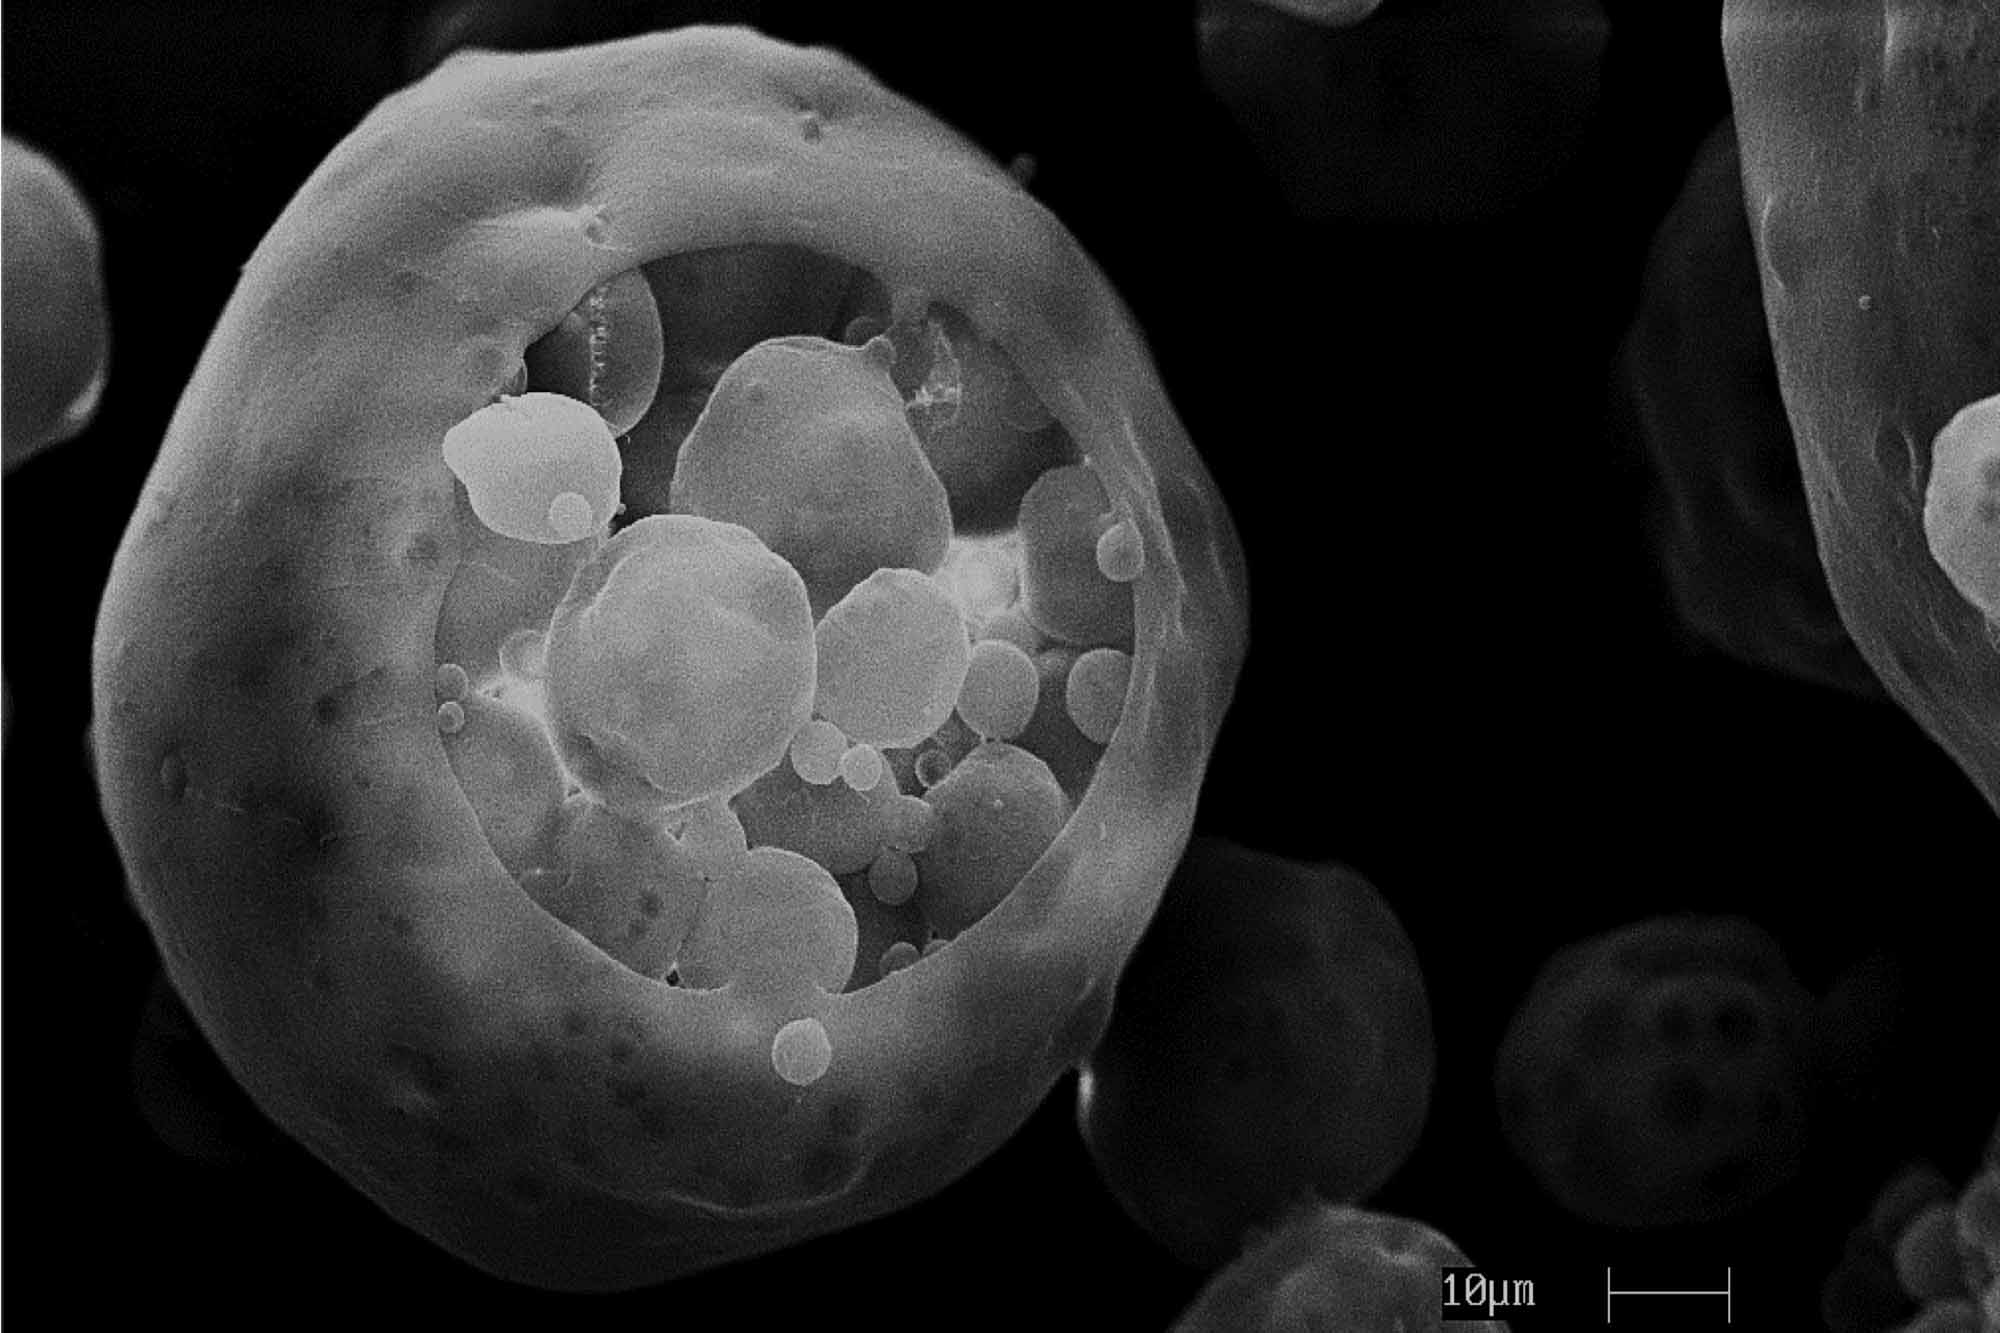

Drug Delivery and Nanomedicine

Designing systems to deliver medicines and measure their effects.